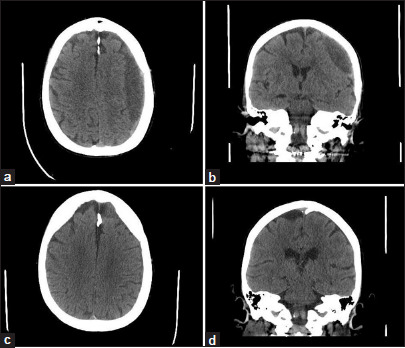

Results: 64 patients were included in the analysis, with a median age of 76 years (interquartile range [IQR]: 68-80). The majority of embolizations (77%) served as primary treatment. The median hematoma depth was 11 mm (IQR 7-15), with bilateral hematomas present in 42% of cases. No intra-procedural complications occurred; however, two patients suffered minor postprocedural complications. The 30-day readmission rate was 5% (n = 3), with no readmissions within 48 h. 17% of patients (n = 11) returned to the ED - the median time from embolization to ED presentation was 12 days (IQR 4-17 days). Among 52 patients (81%) with long-term follow-up, 4% suffered hematoma recurrence requiring surgical drainage, 58% achieved complete resolution of symptoms, and 29% showed improvement in symptoms.

Conclusion: The study suggests that outpatient MMAe can be both safe and feasible for select patients with cSDH.